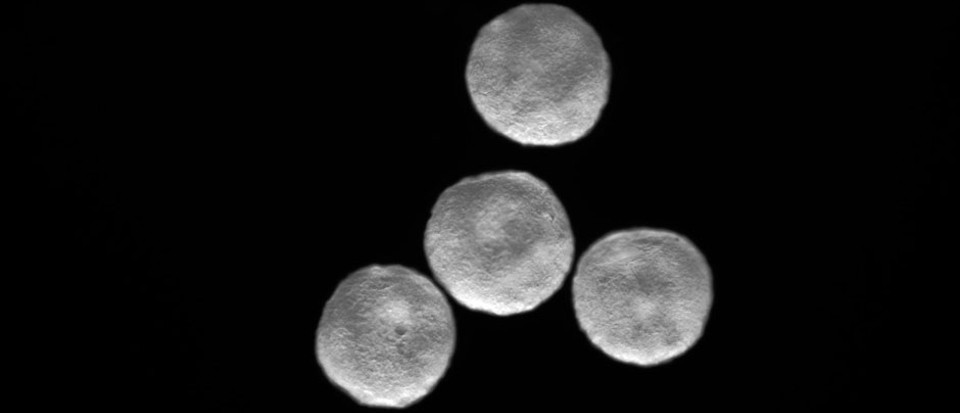

這個人類的“迷你心臟”比芝麻籽還小,卻能以規律的節奏跳動。這是第一個在實驗室里被創造出來的帶有明顯跳動的心室的心臟。這種微型器官或類器官,能模仿25天大的人類胚胎的心臟工作,有助于解開許多謎團,包括為什么嬰兒心臟病發作后其心臟不會留下疤痕。

發育1周后,類器官在結構上相當于25天胚胎的心臟。在這個階段,心臟只有一個心室,這將成為成熟心臟的左心室。類器官直徑約為2毫米,包括這一發育階段常見的主要細胞類型:心肌細胞、上皮細胞、成纖維細胞和心外膜。它們也有一個清晰的心室,每分鐘跳動60到100次,這與相同年齡的胚胎心臟的速率相同

對于此次創造出的迄今為止最真實的心臟類器官,Mendjan 表示,當其第一次看到它的時候,很驚訝這些心室可以自行形成。相比其他類器官,心臟類器官的成敗顯而易見,它會跳動。迄今為止,這顆“迷你心臟”已經在實驗室中存活了3個多月,它將幫助科學家們了解心臟發育的前所未有的細節。